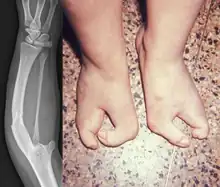

| Other names | Severe ulnar aplasia and lobster claw feet, familial ulnar aplasia and lobster claw syndrome, complete absence of the ulna and of fingers 2 to 5, together with lobster-claw deformity of the feet [1] |

| Symptoms | Ectrodactyly of the hand and ulnar aplasia, Split foot malformation |

Van Den Berghe Dequeker syndrome, also known as ulnar hypoplasia-split foot syndrome is a very rare congenital limb malformation syndrome which is characterized by severe ulnar hypoplasia, absence of the index to pinky finger in both hands, and split-foot.[3]

It was first discovered in 1978 by H van de Berghe et al., when they described four males (consisting of three brothers and one maternal nephew) of a two-generation family with a "lobster-claw foot" and an "ulnar defect".[3] The lobster-claw architecture of the foot is described as the I and V toes being the only ones developed, resulting in the appearance of a split-foot. Morphology of the ulnar defect ranged from a shortened ulna to complete absence of the ulna with a curved, thickened radius. Van de Berghe et al. also noticed that some female members (the mother and maternal aunt of an affected male) showed minor hypoplasia and slight deformations of the toes, as well as shorter ulnas and marginally curved radii. At the time of discovery, ulnar aplasia occurred sporadically and infrequently, therefore, the documentation of this occurring familially was considered to be rare.[3]